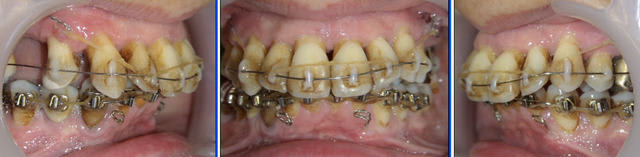

Voici le cas à 3 semaines. Les diastèmes sont complètement fermés.

J’ai rajouté une traction au niveau des incisives centrales. Il y a donc pour le même groupe de dents deux tractions, une au niveau des canines et une autre au niveau des centrales.

Voyez la qualité de la cicatrisation au niveau de l’émergence de la ligature de la muqueuse inférieure.

A trois mois (photos f0), remplacement du fil élastique par un fil NiTi enfilé dans les lumières de composite. Un chaînette élastomérique continue la traction.

A six mois (photos f1, f2 et f3), résultats à ce stade et panoramique de contrôle.